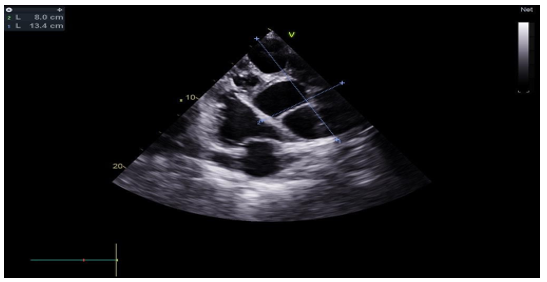

The transthoracic echocardiographic examination revealed (Figures 8 – 18):

- A lobulatedcystic image exerting severe compression on both the right and left cardiac chambers, resulting in hemodynamic disturbance and considerable fluctuation in respiratory flows (Figures 12 – 13,17).

- Left ventricule showed no sign of dilatation. Al though the assessment of contractile function was influeced by compressio from pulmonary hydatid cyst, it appears to maintain functionnality.

- Elevated left ventricular filling pressure were noted.

- The right ventricle exhibited no dilation (Figure 11) despite the presence of longitudinal systolicdys functio n (Figures 14).

- Grade II tricuspid insufficiency was identified, with an estimated systolic pulmonary arterial pressure of 47 mmHg (calculated as 37 + 10 mmHg), indicating the presence of pulmonary hypertension.

- The inferior vena cavademonstrated no dilation (Figure 18) and wasnoted to be non-compliant (Figure 16).

- No pericardial effusion was present.